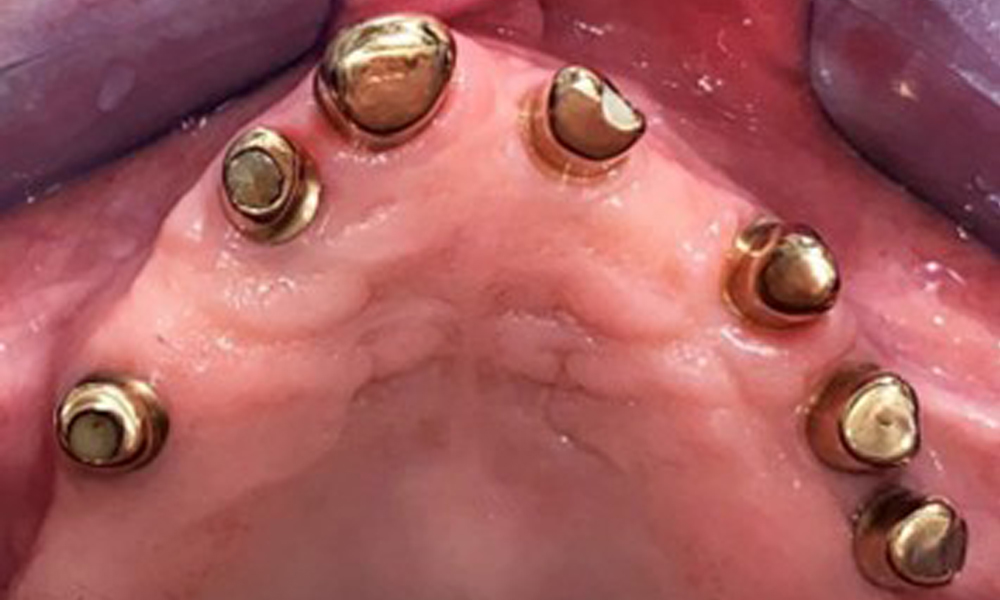

Оклузален изглед: Горна челюст със зъб и телескопични протези, поддържани от импланти

Фиг. 2: Оклузален изглед: Горна челюст със зъб и телескопични протези, поддържани от импланти

Оклузален изглед: Горна челюст с подвижна протеза без небце.

Фиг. 3: Оклузален изглед: Горна челюст с подвижна протеза без небце.